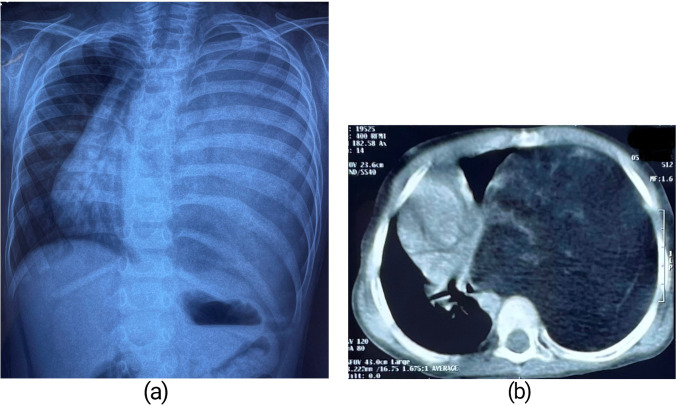

Chest X-ray posteroanterior view revealed a huge homogenously opacified lesion completely occupying the left hemithorax with gross mediastinal shift towards the right side (Fig. 1a). Contrast-enhanced computerized tomography (CECT) of the thorax confirmed a large heterogeneous fat density lesion measuring 125 mm × 106 mm in cross section and 175 mm in craniocaudal dimension, occupying the entire left hemithorax causing significant mass effect with near complete compressive collapse of the left lung sparing only part of the upper lobe and mediastinal shift to the right side (Fig. 1b). The lesion appeared well marginated, and had internal septations and strands with few areas of focal calcification. The left hemidiaphragm was pushed downwards and inverted by the lesion. There was no extra-thoracic extension. Computerized tomography (CT)–guided fine-needle aspiration cytology (FNAC) smears from the lesion showed lobules of mature adipocytes with few capillaries and scanty foci of haemorrhage. Laboratory workup was normal with regard to white cell count, haemoglobin, C-reactive protein (CRP), and erythrocyte sedimentation rate (ESR). An electrocardiogram showed normal sinus rhythm with an isoelectric pattern.

Fig. 1.

(a) Chest X-ray showing complete opacification of left hemithorax. (b) CT scan showing large heterogeneous fat density in left hemithorax